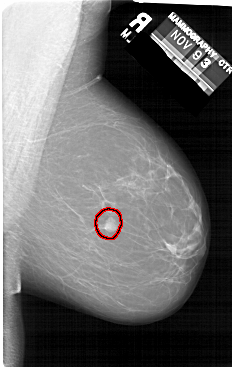

FILE: A_1412_1.RIGHT_MLO.OVERLAY

TOTAL_ABNORMALITIES 1

ABNORMALITY 1

LESION_TYPE MASS SHAPE IRREGULAR MARGINS CIRCUMSCRIBED

ASSESSMENT 4

SUBTLETY 5

PATHOLOGY BENIGN

TOTAL_OUTLINES 1

BOUNDARY

RIGHT_MLO LINES 6601 PIXELS_PER_LINE 4171 BITS_PER_PIXEL 12 RESOLUTION 43.5 OVERLAY